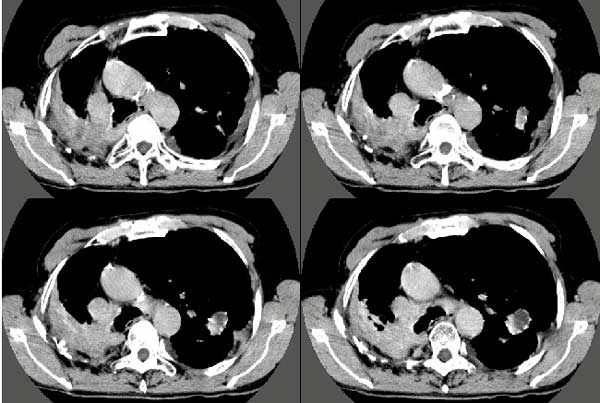

以下是引用扬仪在2005-5-12 20:46:40的发言:[br]右肺呈术后改变;双侧肺野散在分布斑片状、点状高密度病灶,(似可见“树芽征”);左上尖后段见斑团状高密度病灶(2个层面?),边缘毛糙,段性分布,与斜裂相邻,临近胸膜粘连;增强示病灶边缘强化,内呈水样密度;心影、纵隔右移,内可见4r淋巴结肿大。[br]意见:1、双肺继发性肺结核,左上为干酪病灶;[br] 2、矽肺合并感染;[br] 3、建议抗痨+抗炎。 [br]愚人之见,请高人指教!